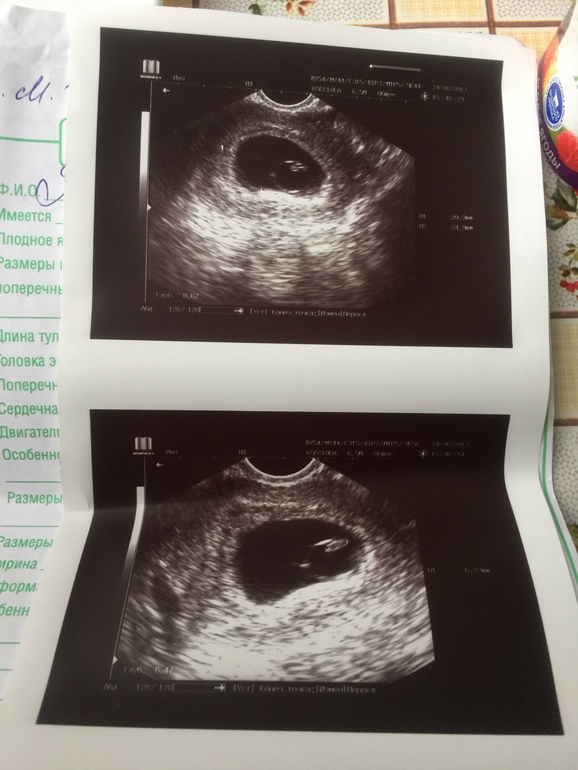

Эмбриончик почти не вырос за неделю(он и в тот раз у вас очень плохо вырос,хотя они очень быстро растут на таком сроке...

У меня так было. Один врач поставил ЗБ и отправил на чистку. Перед чисткой на УЗИ нашли сердце. Врач не поверил, сделал УЗИ ещё раз, тоже нашёл сердце, но сказал, что сердцебиение слабое.

Через неделю начался выкидыш.